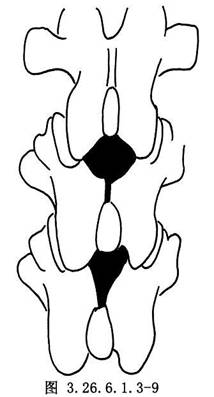

(2)胸椎部分:除切除胸椎棘間韌帶外,尚需將覆蓋在椎板間隙上的棘突咬除,才能進行黃韌帶開窗術。由於胸椎椎間隙較狹窄,常需咬除部分椎板以擴大骨孔。在主彎頂部附近的幾節椎板間隙,可將凸側椎板楔形切除到關節突,以利脊柱矯形(圖3.26.6.1.3-9,3.26.6.1.3-10)。